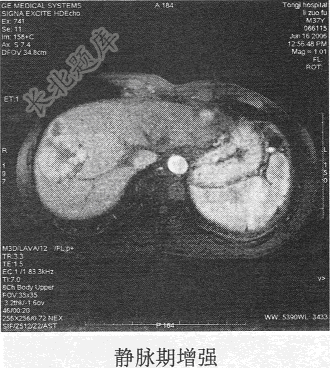

- 单项选择题患者男,54岁。体检发现肝脏占位,MR图像如下,最有可能的诊断是

C、肝血管瘤

D、肝癌